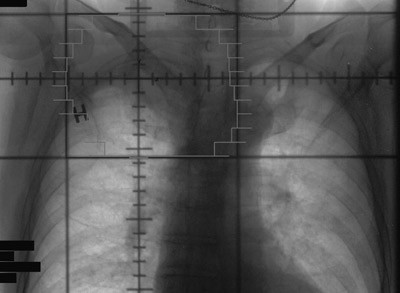

Røntgen thorax (fig 1) tatt rutinemessig ved innkomst viste en oppfylling i høyre lungetopp. CT collum/thorax/abdomen avdekket en ca. 6 cm stor svulst apikalt i høyre lunge (fig 2a, b). Det var ingen tegn til patologisk forstørrede lymfeknuter eller andre svulster. Bildene viste i tillegg emfysemforandringer og et stort abdominalt aortaaneurisme.

På grunn av beliggenheten kan disse svulstene være vanskelig å oppdage ved konvensjonell røntgenundersøkelse. Det ses ofte kun apikal pleurafortykkelse med asymmetri av lungetoppene. Fordi skuldersmerter er et av de mest typiske symptomene, blir mange initialt behandlet for antatte muskel-skjelett-plager, og symptomene kan vedvare i måneder før videre utredning igangsettes. Forsinket diagnose bidrar til at de fleste av disse svulstene oppdages i et avansert stadium – noe som har konsekvenser for overlevelsen (2). I et materiale fra Attar og medarbeidere var median overlevelse ved T3-sykdom 36,8 måneder, 6,4 måneder ved T4-sykdom (10).